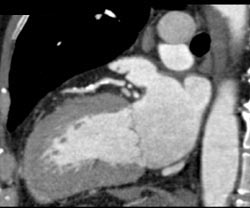

Diagnosis

LAD Plaque